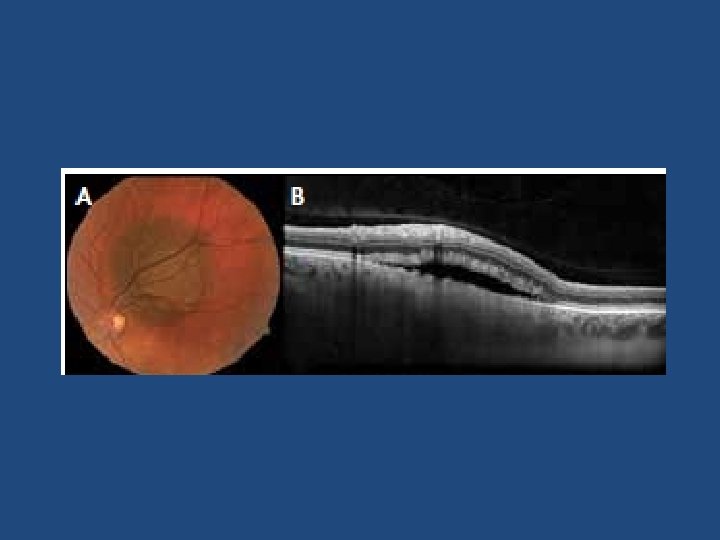

Suspicious OCT findings • • • Intra retinal oedema Shaggy photoreceptors Loss of ELM Loss of IS/OS junction (p=0. 003) (p=0. 005) (p=0. 008) (p=0. 02)

Ultrasound vs OCT-EDI • OCT-EDI measurements are approximately 50% less thick than USB measurements (i. e. a 3 mm lesion on USB will measure 1. 5 mm on OCT-EDI) • USB cannot detect/measure lesions <0. 75 mm thick – these can be measured with OCT-EDI • OCT-EDI less helpful as tumours enlarge (>3 mm) • The lesion must be at least 1. 5 mm thick on USB measurement before meaningful comments on echogenicity can be made • USB echogenicity is determined by the density of cellularity of the tissue comprising the lesion (the denser the tissue the lesser the internal reflectivity) • OCT-EDI appearance is determined by the amount of pigment in the lesion and does not correlate to ultrasonic internal reflectivity • OCT-EDI offers a better estimate of the true dimensions of the lesion compared to USB